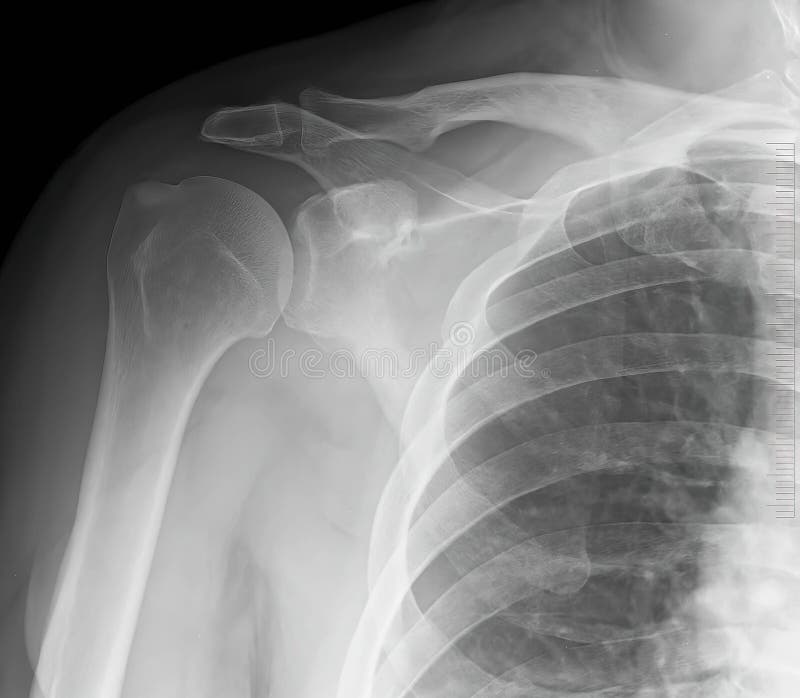

Inferior subluxation of the humerus Image

from radiopaedia.org